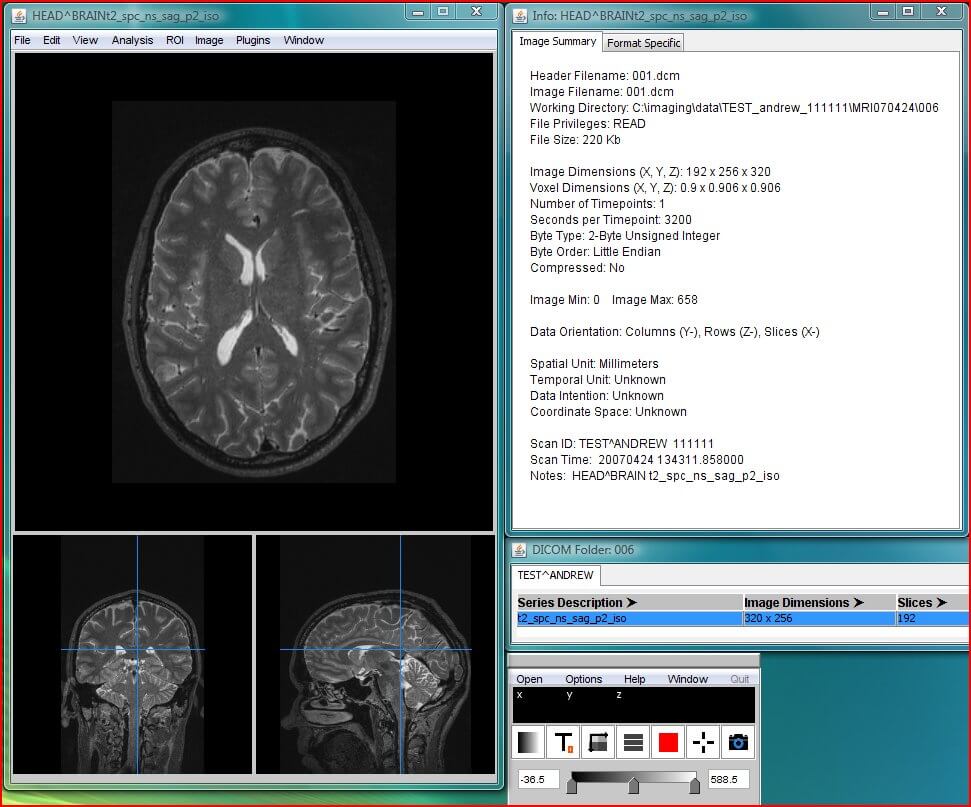

MANGO is an advanced DICOM application which requires some technical coding before it can be used. It has several advanced features, including conversion, anonymization and editing images. Other versions of Mango (Papaya and iMango) can be accessed from the browser directly or an Apple iPad. The application is under constant development, possible due to grants from the National Institute of Mental Health and the National Institute of Biomedical Imaging and Engineering. Therefore, it keeps improving in its functionality. Advanced options like behavioral analysis, disease analysis, and brain separation modalities make it particularly useful for neuromedicine. It does not offer cloud storage.

| 9. | MANGO | Windows, Mac OS X, Linux | Not available | Y | Y | Y | N.A. | N.A. | Intel core/ 4 GB RAM | Free for non-commercial use |